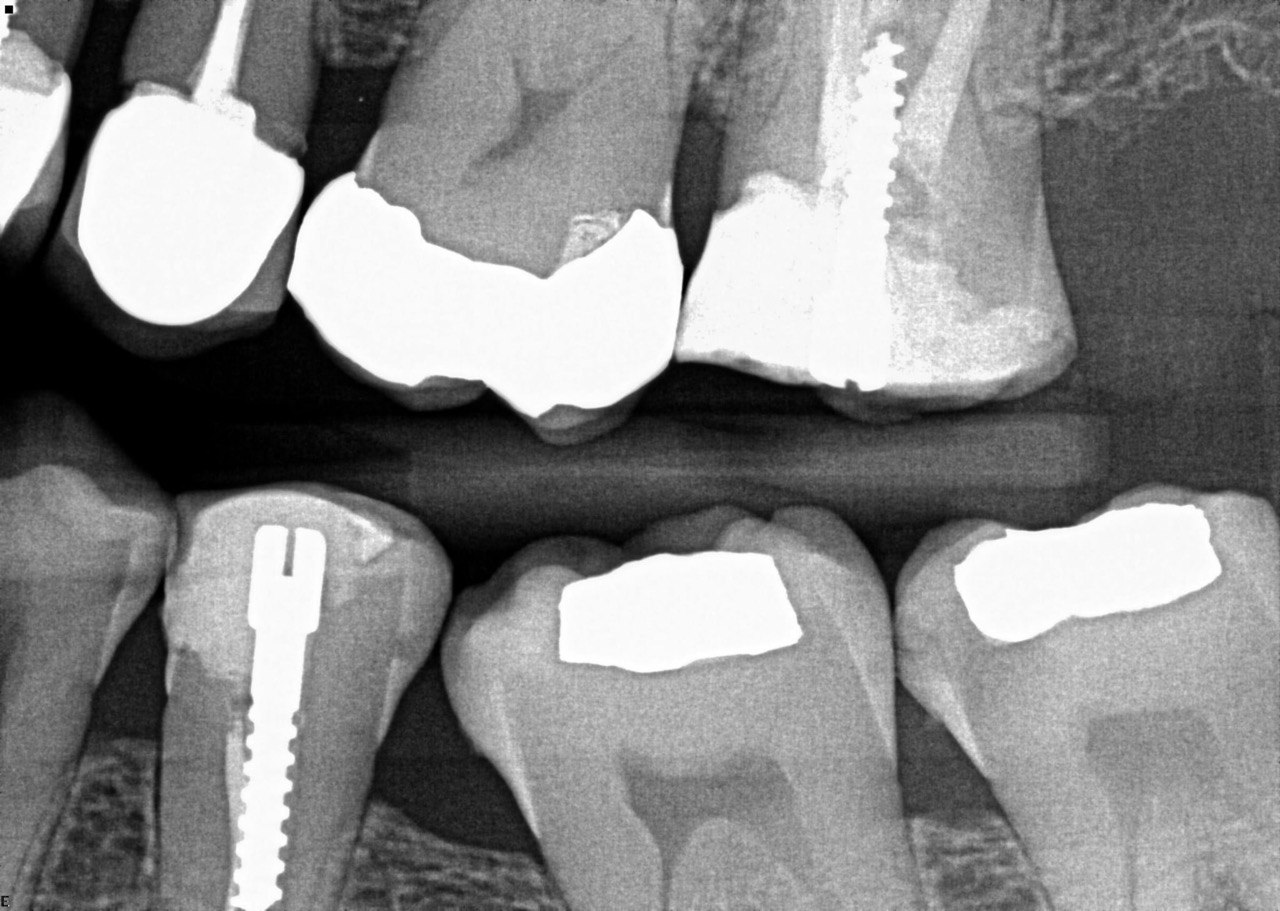

Question 1: What is the condition of the mesial surface of the tooth # 2.6?

Question 2. What is the condition of the mesial of the tooth # 2.7?

Question 3. What is the condition of the distal surface of the tooth # 2.7 and mesial surface of the tooth # 2.8 respectively?

Question 4: what is the condition of the distal of the tooth # 4.1 and mesial of the tooth #3.1 respectively?

Question 5: Which surface shows recurrent caries?

Question 6: Which surface shows recurrent caries?